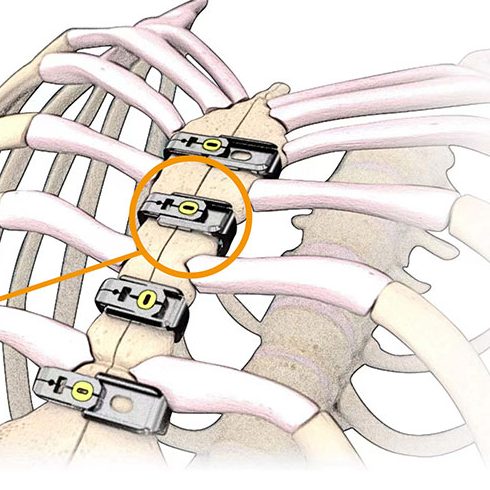

Unsere Methode - sternumerhaltend und schonend

Im Zentrum steht eine externe Stabilisierung des Brustbeins, die ohne Schrauben im Knochen auskommt.

Vorteile für die Patienten

- keine zusätzliche Knochenverletzung

- Schonung des umliegenden Gewebes

- Stabilisierung durch kontrollierten äußeren Druck

- Patientenspezifische Implantate-Auswahl (Claw®, Teflon-Bänder, Embrace®,3d-geprintete Titan-Implantate)

- Jederzeit schonend reversibel, z.B. im Notfall

- Sehr gut geeignet bei Risikopatienten, z.B. Osteoporose, Diabetes, COPD, Übergewicht